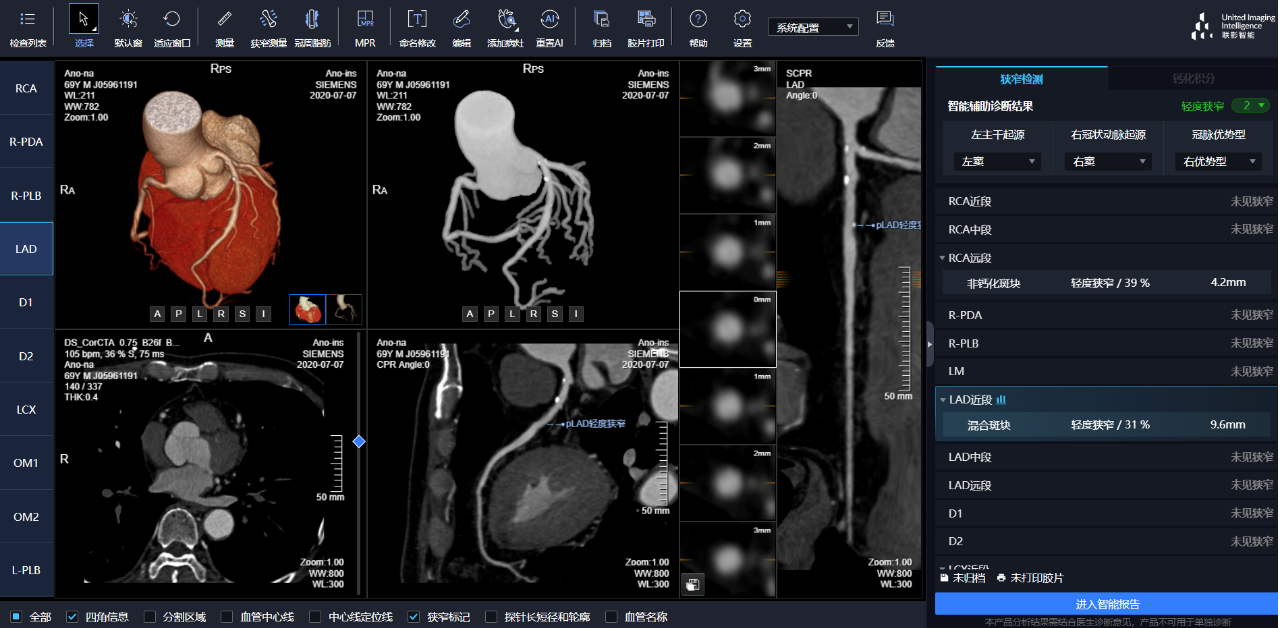

通過3D視圖可任意旋轉(zhuǎn)觀看血管全貌,AI秒級實(shí)時(shí)計(jì)算重建血管,可實(shí)現(xiàn)多維輔診包含:板塊定性定量分析、狹窄評估、心肌橋檢出、支架檢出、鈣化積分,全程AI關(guān)注心血管健康。